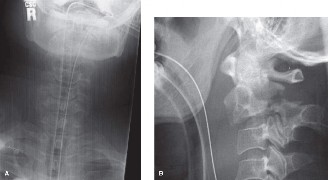

Recognize surgical and nonsurgical indications for a thoracic lymphoma? Definitively manage a thoracic lymphoma? CASE 13 A 23-year-old man was involved in a high-speed motor vehicle accident. On presentation to the trauma bay, his chief complaint was neck pain. Physical examination demonstrated that he was neurologically intact. Images of the cervical spine are shown in Figure 1–19A–B. Full workup demonstrated no other injuries.

Figure 1–19 A–B

The correct answer is (B). The imaging clearly demonstrates a Hangman’s fracture, also known as a C2 traumatic spondylolisthesis. The hallmark of this injury is a fracture through the pars interarticularis of C2, which effectively dissociates the anterior elements from the posterior arch and facet joints. A Jefferson fracture refers to C1 ring fractures that can have varying degrees of lateral displacement. There is no evidence of vertebral body comminution with posterior vertebral body involvement, which would be characteristic of a burst fracture. While some Hangman’s fractures can be associated with facet dislocation, there is no evidence of this on the imaging.

What is the classification for this fracture?

The correct answer is (B). Type I fractures have minimal horizontal displacement, no angulation, and the C2–3 disc remains intact. Type II fractures are both displaced and angulated, presumably hinging around the anterior longitudinal ligament. Importantly, these fractures reduce with longitudinal traction. Type IIA fractures have minimal horizontal displacement but are significantly angulated. It is presumed that the anterior fragment rotates in place, most likely disrupting the anterior longitudinal ligament. These injuries are worsened by traction and reduced with axial compression. Type III fractures have bilateral C2–3 facet dislocations.

What is the most appropriate definitive treatment for this patient?

The correct answer is (B). While type I fractures can be treated immediately in a hard collar, type II fractures are best treated initially with traction to achieve fracture reduction. After a short period of traction, the patient should be placed in a halo vest to allow mobilization. As indicated above, type IIA fractures should not be placed in traction; patients should be placed in a halo vest with some axial compression applied. Type III fractures require surgical reduction of the facet dislocation and internal stabilization. Objectives: Did you learn...? Identify a Hangman’s fracture based on imaging? Understand the classification of Hangman’s fractures?